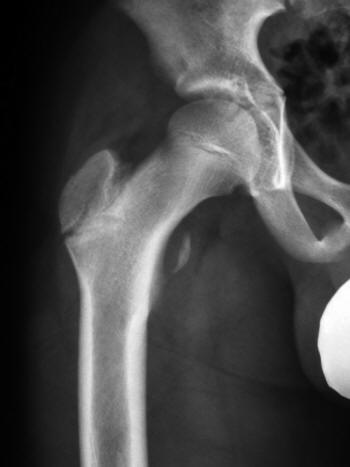

Avulsion fracture of left lesser trochanter at the insertion of the iliopsoas tendon. All lesser trochanteric avulsions can be treated nonoperatively. Avulsion fracture of lesser trochanter of the femur is a well known entity in children and adolescents 1 . Pelvic, pelvis, avulsion, fracture, athlete, hurdler, sprinter, runner, radiology. The lesser trochanter and linea aspera are posterior. Avulsion in adolescence is probably due to avulsion of the iliopsoas tendon. • for isolated femoral heads greater trochanter avulsion; Adolescent, avulsion fracture, hip pain, lesser trochanter.

Intertrochanteric means between the trochanters, which are bony protrusions on the femur (thighbone). Avulsion fractures of the lesser trochanter in adolescents are rare, representing less than 1% of hip injuries in the orthopedic surgeon's practice. Lesser trochanter avulsion fracture (site of iliopsoas muscle insertion). All lesser trochanteric avulsions can be treated nonoperatively. Lesser trochanter avulsion, apophysis, groin pain. An acute avulsion causes severe functional impairment with compromised hip flexion. Implant failure occurs within the first three months. An intertrochanteric fracture occurs along a line that is located between the greater and lesser trochanters. However, its fracture or progressive radiolucency is considered a pathognomic finding in adults with malignancies 2 . This can occur at the ligament by the application of forces external to the body (such as a fall or pull). An unusual cause of hip pain in an adolescent.}, author={e. It usually occurs during vigorous sport activity. Adolescent, avulsion fracture, hip pain, lesser trochanter.

Avulsion fractures of the lesser trochanter in adolescents are rare, representing less than 1% of hip injuries in the orthopedic surgeon's practice. In this situation, reduction and fixation may need to be considered. This injury is a result of a sudden forceful contraction of the iliopsoas tendon. Lesser trochanter avulsion fracture (site of iliopsoas muscle insertion). The greater trochanter and the lesser trochanter. Case contributed by dr mark holland. An intertrochanteric fracture is a specific type of hip fracture. Avulsion in adolescence is probably due to avulsion of the iliopsoas tendon.